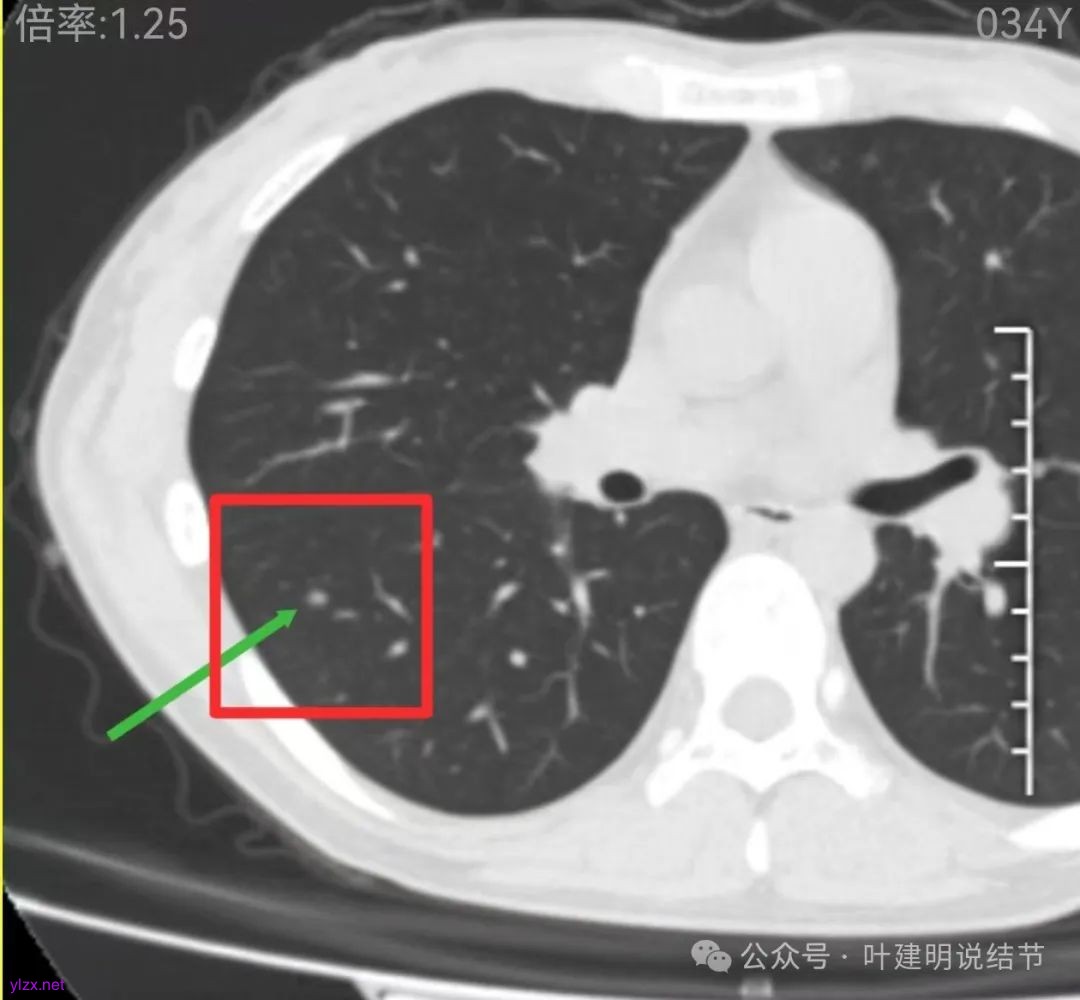

再看中间2023年的影像:

右下此灶2023年时此层面淡而边显糊。

上图层面已经像混合密度了,表面毛糙不光滑,灶内密度不均,也有小空泡征的样子。

感觉这处(在上截图结节的下面点,邻近层面)不像前面病灶的延伸,否则这密度的变化有点突兀呀。

两肺多发结节,左侧黄色标注的考虑是肺泡上皮增生可能性大;蓝色的考虑肺泡上皮增生或者少许慢性炎可能性大;右侧红色宽起来并带有红色箭头的这处是主病灶,偏混合密度,整体轮廓较为清楚,边缘显得毛糙,从2024年12月份的来看,要考虑是肿瘤范畴,原位癌或者微浸润性腺癌可能性较大,也不能完全排除不典型增生。但是在2022年的时候,这个病灶的边上也有一个实性的微小结节,如果只看2022年的,这么小的实性结节,又比较圆,表面也显得较为光滑,是要考虑良性的,当然太小了需要动态观察。回头再重新来看2024年底的,发现绿色箭头所指的这个微小实性的较2022年几乎没有变,去仔细寻找2022年的,发现当时在实性结节旁边也有密度很淡的一点磨玻璃影(也可能真的就是一处,只是扫描不够薄,密度的变化有些突兀而已),而到了2024年12月份,实性微小这处没有明显变化,但是原来很淡的磨玻璃变成了混合磨玻璃,范围也明显扩大。所以总体来看右肺下叶这处是考虑恶性的,而且从磨玻璃结节角度来讲,还是生长比较快的,就是说还是有一定风险的。加上左侧还有两处也是磨玻璃持续存在,虽然边缘轮廓显模糊一点,但多年以后也可能仍然要变成原位癌或者微浸润性腺癌之类的东西。通盘考虑以后,我倾向于右侧近期单孔胸腔镜下微创局部切除,左侧随访观察,等到有进展并风险增加再来考虑处理。意见供参考!